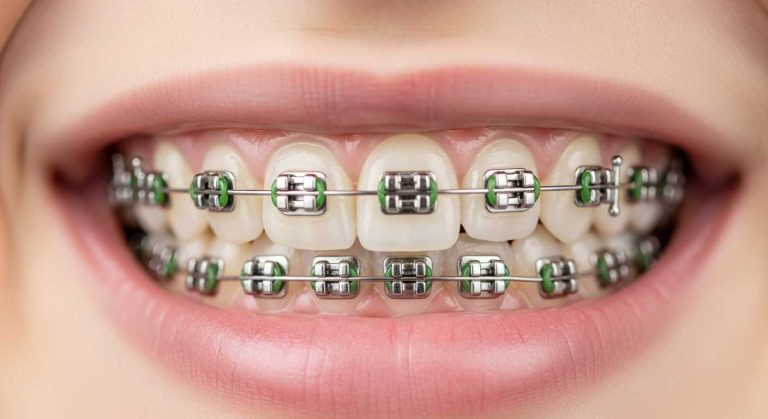

- ارتودنسی ثابت: استفاده از براکت های فلزی، سرامیکی و دیمون برای اصلاح انواع ناهنجاری ها.